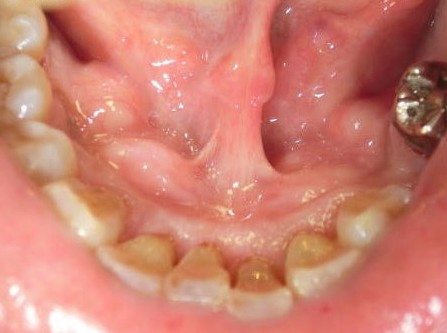

(2)過剰な上顎結節

上顎結節の一部が尖っていて、入れ歯が出し入れの時に痛み、入れ歯も安定しませんでした。

骨の鋭縁分を削って義歯も安定し、痛みも無くなりました。